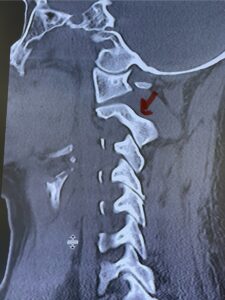

This is a 59 year-old female with a history of cerebral palsy and a prior C3-C7 posterior cervical laminectomy and instrumented fusion two years prior. She did ok until she developed progressive weakness of all four extremities and numbness. Imaging revealed she had a significant breakdown above the fusion at C2-3 with a grade 2-3 spondylolisthesis of C2 on C3 with severe spinal cord compression (Fig. 9). It was surprising the degree of anterior fusion induced by the posterior fusion from C 3-C 7 (Fig. 10). Because of her progressive neurological dysfunction in a patient who was already compromised because of her cerebral palsy, it was clearly necessary to decompress from occiput to C 3. We utilized her prior lateral mass screws although we removed bilaterally the C7 screws to reduce the fulcrum-effect on the C7-T1 junction as the C 6-7 level was solidly fused. We performed an occiput to C 6 fusion with occiput to C3 laminectomy (Fig. 11) Post operatively we had good placement and alignment (Fig. 12) The patient went to rehab with improvement of strength and numbness particularly in hands.

Fig. 10: Sagittal cervical CT scan demonstrating grade 2-3 subluxation of C2 on C3 above prior C3 to C7 posterior instrumented fusion and laminectomy (red arrow). Note the unusual significant anterior auto fusion resulting from prior posterior construct (red dot).